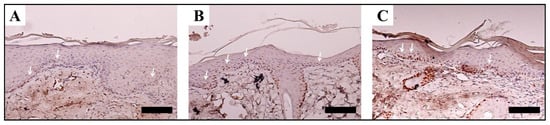

- Schneider, A.; Wang, X.Y.; Kaplan, D.L.; Garlick, J.A.; Egles, C. Biofunctionalized electrospun silk mats as a topical bioactive dressing for accelerated wound healing. Acta Biomater. 2009, 5, 2570–2578. [Google Scholar] [CrossRef]

- Gil, E.S.; Panilaitis, B.; Bellas, E.; Kaplan, D.L. Functionalized silk biomaterials for wound healing. Adv. Healthc. Mater. 2013, 2, 206–217. [Google Scholar] [CrossRef]